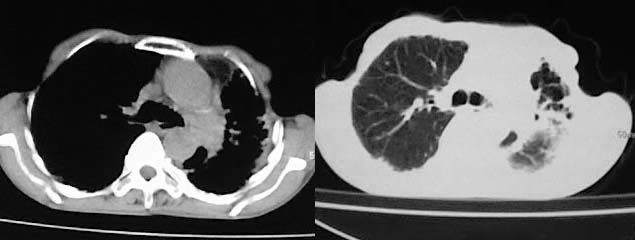

以下是引用有风的日子在2008-5-2 12:13:00的发言:[br][emb10][br][br]肺ca?有病理支持吗?[br][br]我看更象是肺tb并支扩、间质性肺炎。最好拿个病理结果来,不然这点影像资料诊断肺ca是难以服人的![br][br]至于主动脉瘤的诊断问题,国外认为≥4.0cm就可诊断了,国内对此诊断标准更为严格。患者升主动脉明显增粗,即>4cm。你诊断个升主动脉扩张并不为过!

以下是引用zjzjr在2008-5-2 14:39:00的发言:[br]支持双侧继发型肺结核,左侧胸膜肥厚,慢性支气管炎伴间质纤维化.